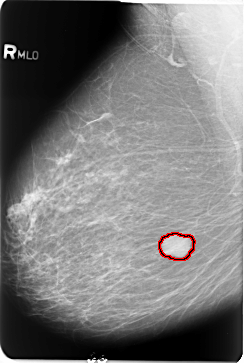

FILE: B_3484_1.RIGHT_MLO.OVERLAY

TOTAL_ABNORMALITIES 1

ABNORMALITY 1

LESION_TYPE MASS SHAPE LOBULATED MARGINS CIRCUMSCRIBED

ASSESSMENT 4

SUBTLETY 5

PATHOLOGY BENIGN

TOTAL_OUTLINES 1

BOUNDARY